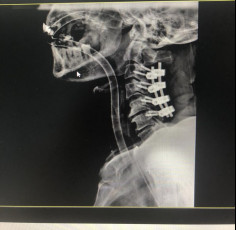

(術(shù)后拍片)

2020年12月4日,在確保張阿伯的身體狀況符合手術(shù)指征后,經(jīng)過(guò)麻醉、手術(shù)、復(fù)蘇,長(zhǎng)達(dá)4個(gè)半小時(shí)的救治,戈才華主任帶領(lǐng)脊柱科醫(yī)療團(tuán)隊(duì)順利地完成了“頸后路減壓椎管擴(kuò)大成形植骨融合術(shù)”。由于患者年齡偏大,手術(shù)強(qiáng)度高,患者失血較多,轉(zhuǎn)入重癥醫(yī)學(xué)科進(jìn)一步監(jiān)護(hù)治療。重癥監(jiān)護(hù)兩天后,張阿伯狀態(tài)良好,生命體征平穩(wěn),轉(zhuǎn)回脊柱科繼續(xù)??浦委煛?/p>

今年5月,張阿伯出院近2月后,大部分生活已經(jīng)可以自理。戈主任為張阿伯做了復(fù)查診治,結(jié)果顯示他的頸椎固定可靠,復(fù)位良好,病體正在朝理想的康復(fù)方向發(fā)展。